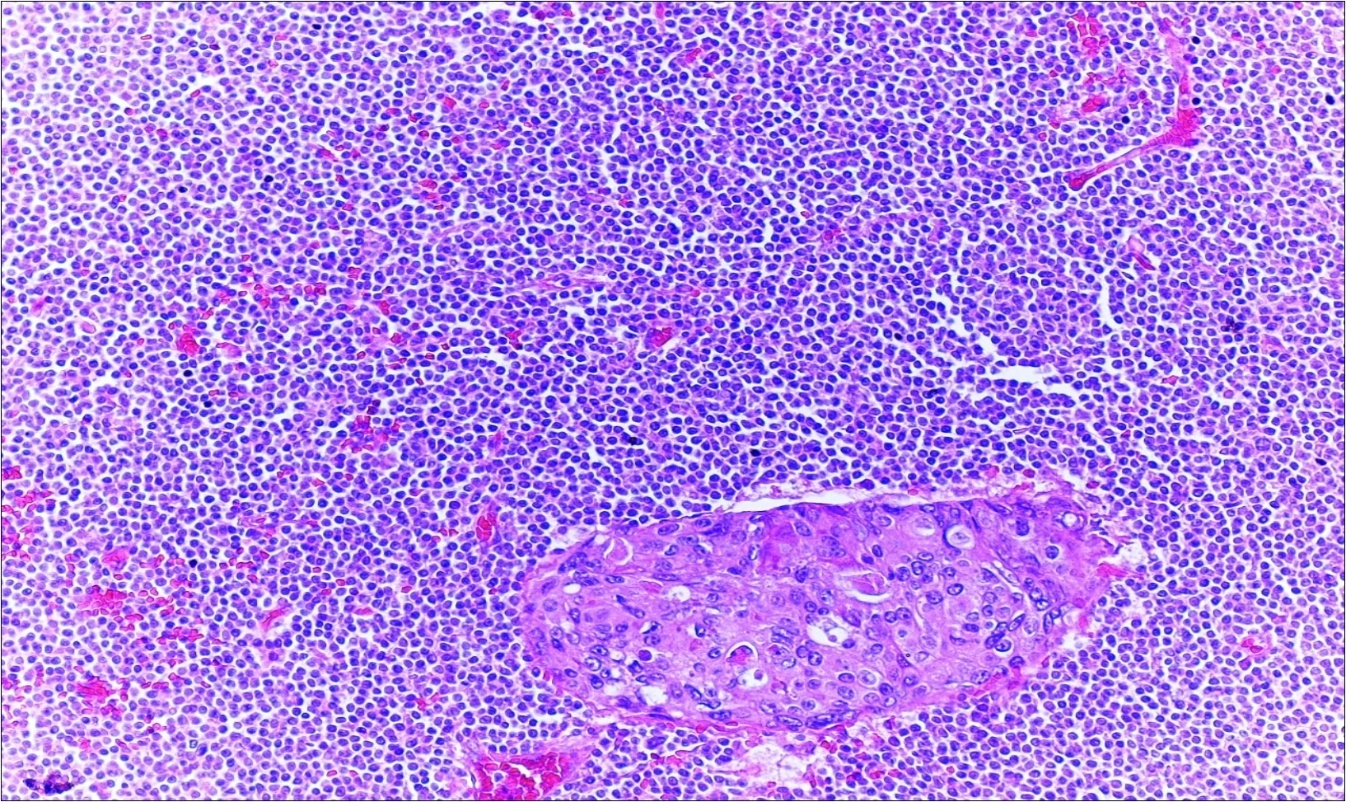

A 63-year-old woman presented to the Department of General Surgery as an outpatient with abdominal pain. Physical examination showed the signs of acute appendicitis and appendectomy was performed. During microscopic examination, a small focus of atypical monotonous lymphoid cell population was seen and the material was sampled totally. The pathological examination revealed MALT lymphoma (Figure 1), with diffuse positivity of cluster of differentiation (CD) 20 (Figure 2), CD 79a and B-cell lymphoma (Bcl- 2) (Figure 3) with just a few CD3 positive lymphoid cells. However, no evidence of adenocarcinoma was found in the appendectomy specimen. After the diagnosis of lymphoma, a complete colonoscopy was planned and this revealed a solid tumoral mass in the caecum measuring 5x4x4 cm. Computed tomography of the abdomen and pelvis revealed mesenteric lymphadenopathy associated with a mass in the caecum with multiple nodules in liver consistent with metastasis (Figure 4). Frozen sections were not obtained since the treatment method would not be affected. The patient underwent anterior resection with regional lymphadenectomy, with the pathological assessment of the resected specimen revealing a collision tumor consisting of a poorly differentiated adenocarcinoma extending through the muscularis propria with MALT lymphoma (Figure 5). Microscopic evaluation of the 11 regional lymph nodes in the mesentery of the resected colon and liver biopsy showed diffuse infiltration of MALT lymphoma with metastasis of adenocarcinoma (Figure 6). According to immunohistochemistry, atypical lymphocytes were positive for CD 20, Bcl-2, and negative for CD3, CD5, CD10, CD23, Bcl-6, terminal deoxynucleotidyl transferase, and cyclin D1. The proliferation fraction (MIB-1 immunostaining) was approximately 20%. The morphological and immunohistochemical findings were used to confirm the diagnosis of synchronous presentation of MALT lymphoma and colon adenocarcinoma within the caecum, mesenteric lymph nodes and liver metastases.

Figure 1.Appendix lumen infiltrated with B lymphoid cells (h&e;x100)